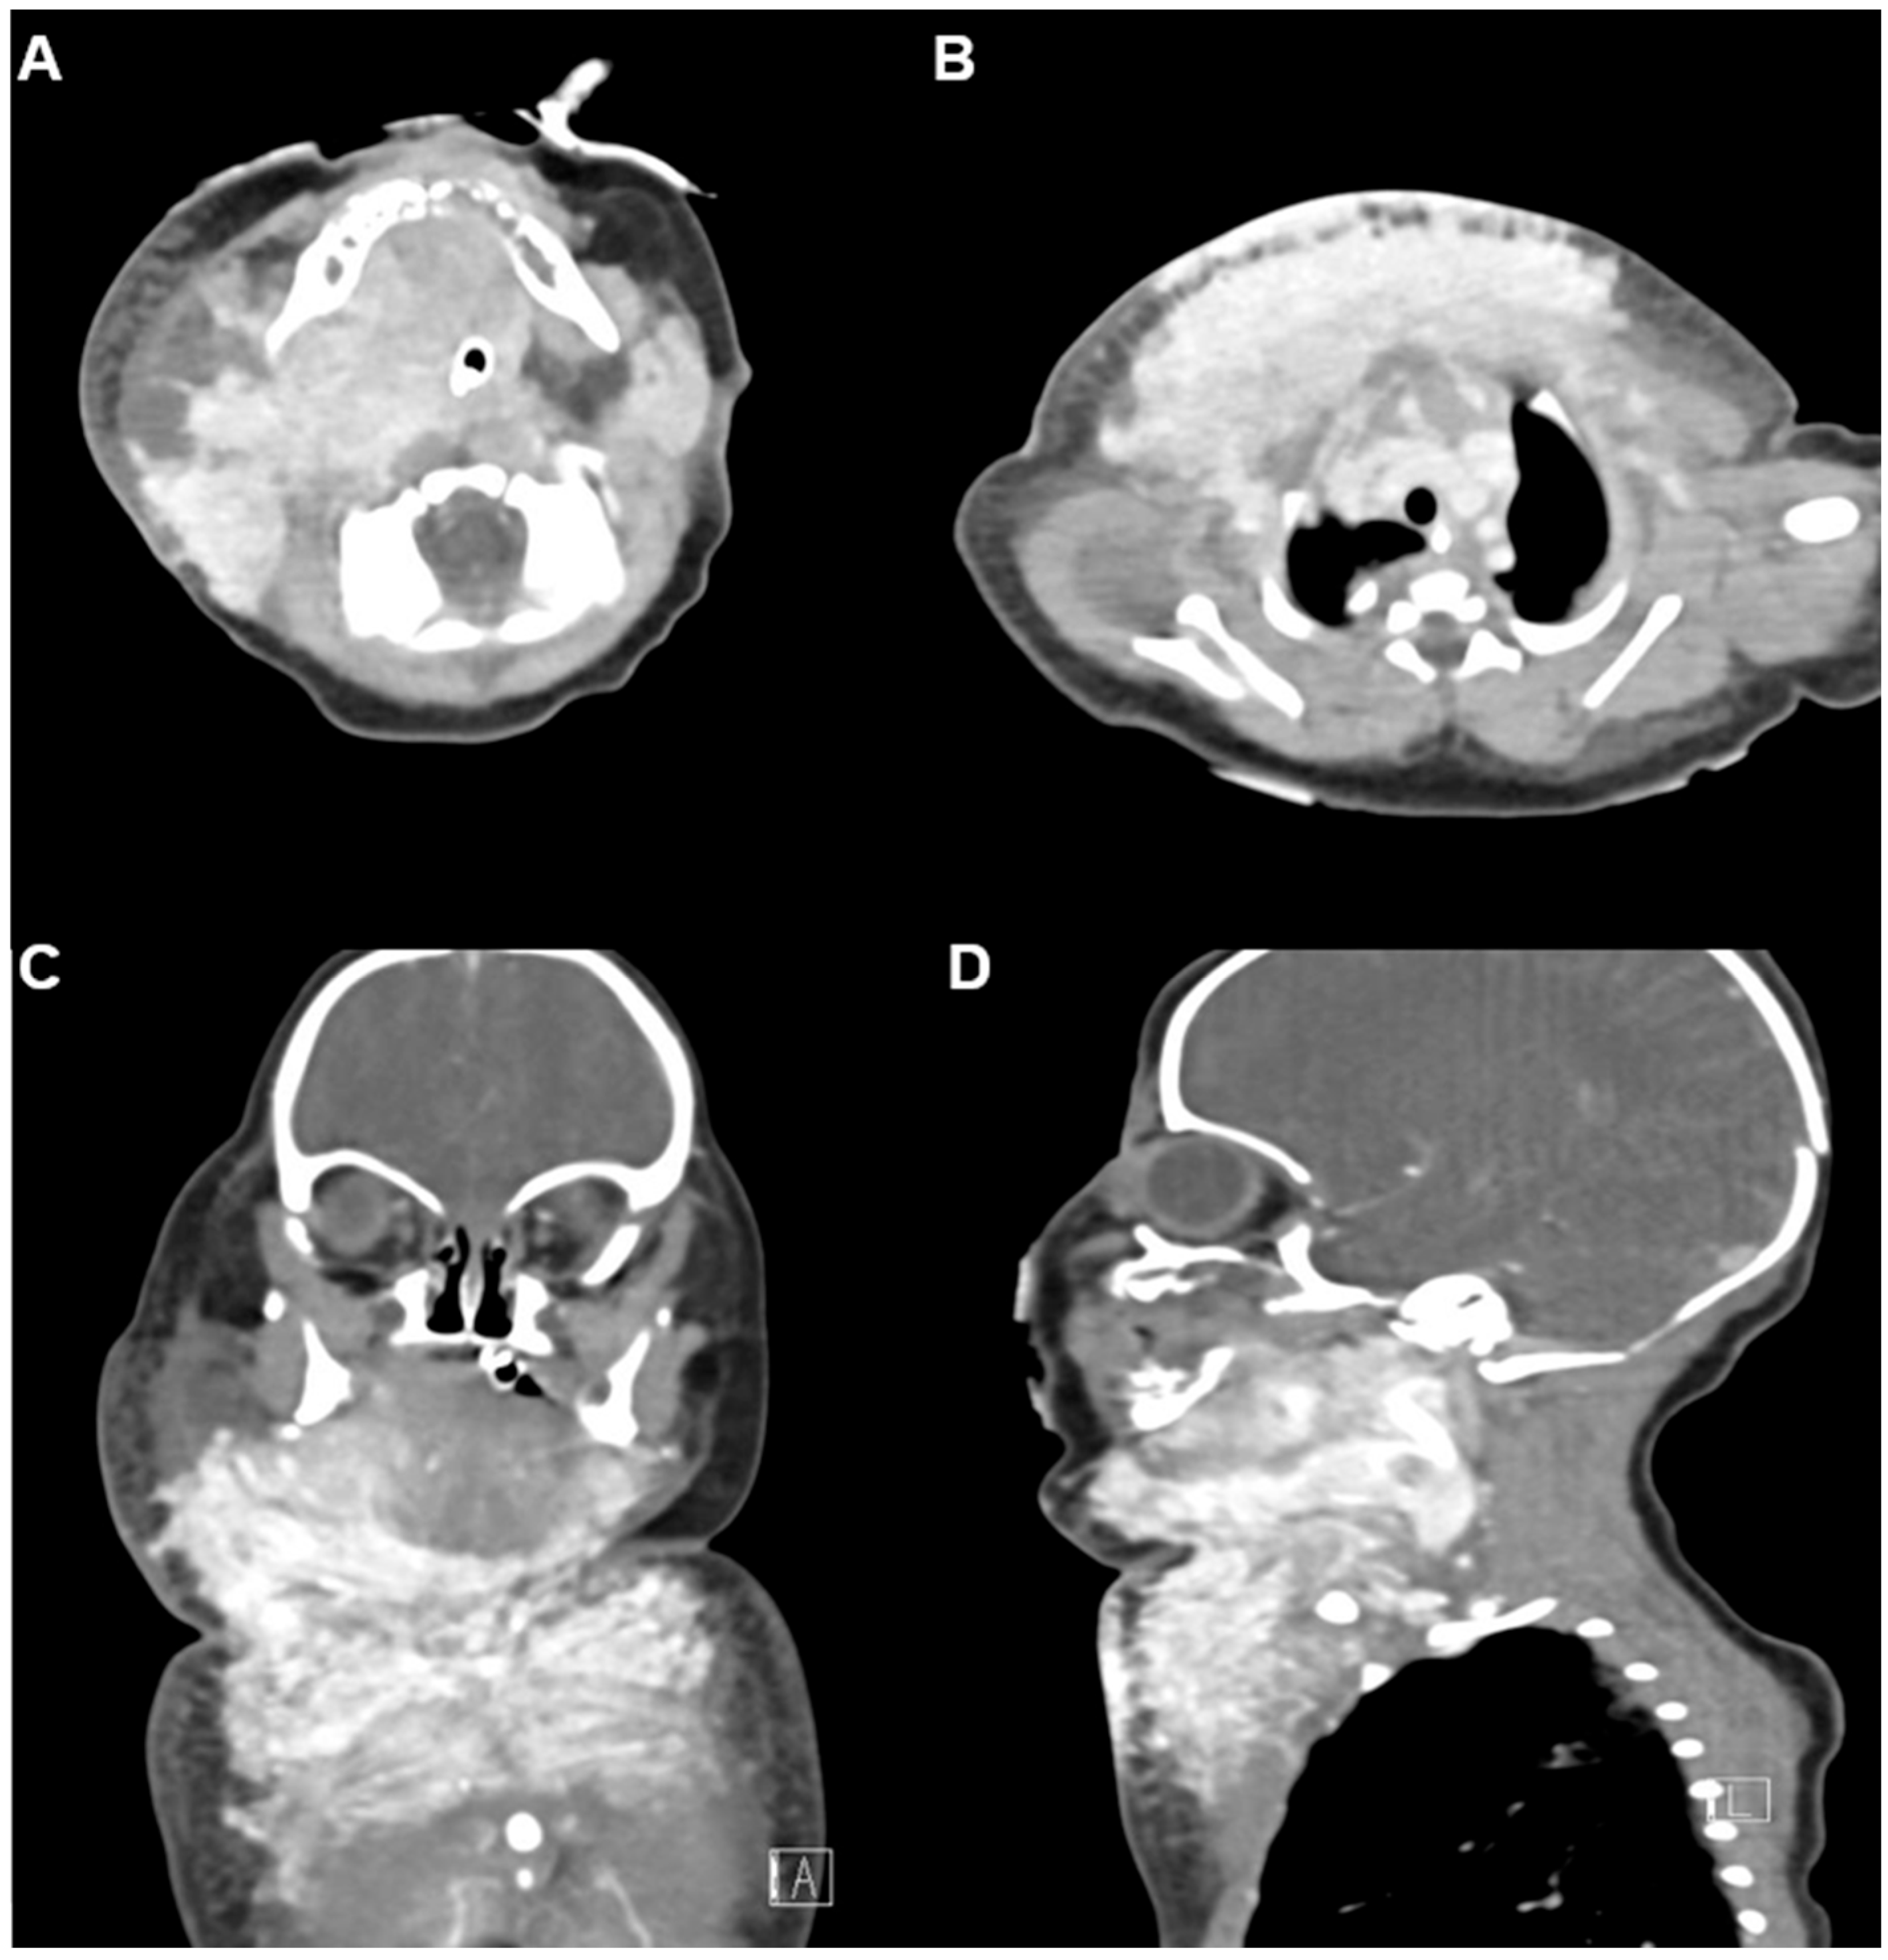

Neck and chest ultrasonography demonstrated a diffuse, infiltrative, and hypervascular soft tissue mass without cystic components. Contrast-enhanced CT performed at 5 days of life revealed an intensely enhancing infiltrative lesion involving the right parotid, submandibular, lingual, and retropharyngeal spaces, with extension into the posterior cervical compartments and both anterior deep soft tissue layers, further involving the upper anterior chest wall. The respiratory distress was considered to be due to external compression by the lesion rather than direct invasion of the upper airway. Numerous feeding and draining vessels were visualized (Figure 2A–D). These findings, together with the hematologic profile and clinical presentation, strongly supported a diagnosis of kaposiform hemangioendothelioma (KHE) complicated by Kasabach–Merritt phenomenon (KMP). Maternal-fetal antibody screening and immunologic workup were unremarkable, effectively excluding alloimmune thrombocytopenia and other hematologic disorders. Given the severe coagulopathy and associated high risk of hemorrhage, surgical biopsy was deemed unsafe, and a clinico-radiographic diagnosis was established.

Figure 2. Initial contrast-enhanced CT at 5 days of age. (A,B) Axial and mediastinal views demonstrate an intensely enhancing infiltrative lesion involving the right parotid, submandibular, lingual, retropharyngeal, posterior cervical, and both anterior deep soft tissue layers, extending into the upper anterior chest wall. Numerous feeding and draining superficial and deep vessels are evident, consistent with a vascular tumor. Endotracheal tube is in situ. (C) Coronal and (D) sagittal views further delineate the mass with associated subsegmental atelectasis in the left lower lobe.